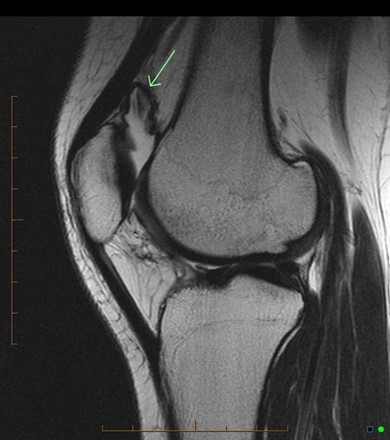

This is an MRI diagnosis and is best appreciated with the full set of images

Case courtesy of Dr. Andrew Dixon, Radiopaedia.org. From the case rID: 41239